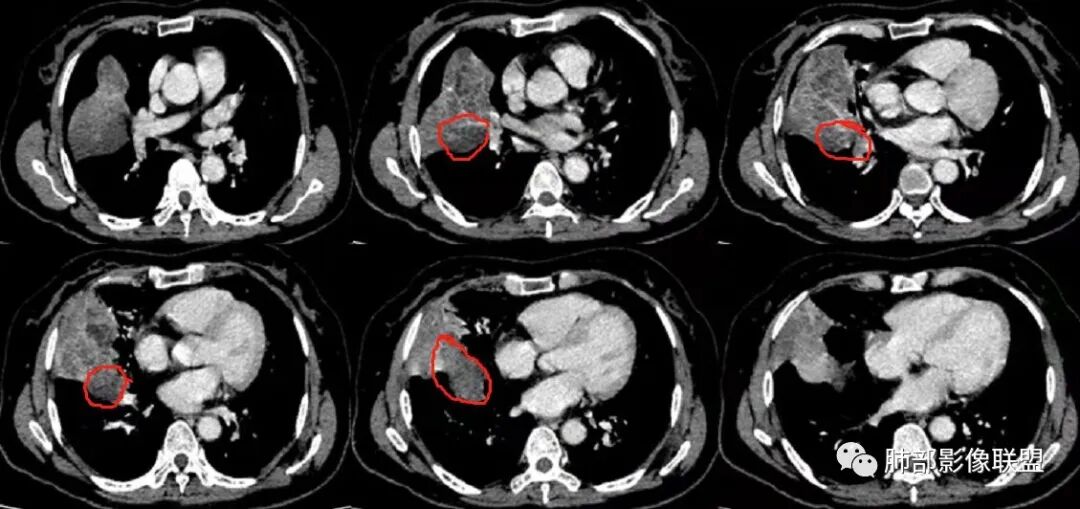

这个病灶中叶、下叶都有

坏死腔是连通的

这个支气管局部堵了,但是远端支气管走形自然,腔内粘液栓

这个病例,看长轴、形态,首先跨叶,里面的坏死腔,它是相通的,就是跨中叶及前基底段。

看中叶外侧段的病变,我观察到支气管与坏死腔相通的,支气管这种堵塞就不踏实了,假如是腔内的病变,就不太支持。

如果是腔内的病变,第一,应该是局限在某个叶的,不可能上下叶都有。所以不太支持腔内的病变。因此考虑腔外的病变。腔外局限的肿瘤肯定不符合,假如这个病灶是个局限大肿块的话,里面肺动脉走势还可以。

然后中叶与下叶的坏死腔病灶是相通的,病灶是跨叶的,胸膜糊墙为主。

我要看一下下叶。还想重建一下,就是按照我自己理解的长轴去重建出这个病灶的整体形态,我当时一看,好像侧向融合的病灶。侧向融合的病灶考虑慢性炎性病变的,有几种,这样大片的病灶,常规都考虑特殊感染多一些,比如隐球,放线菌,奴卡等,都可以这样的改变。

现有的CT,里面存在坏死腔。炎症肯定有,是否同时合并肿瘤的问题?我需要详细的图将内部结构逐步剖析出来,看看能否有新的依据